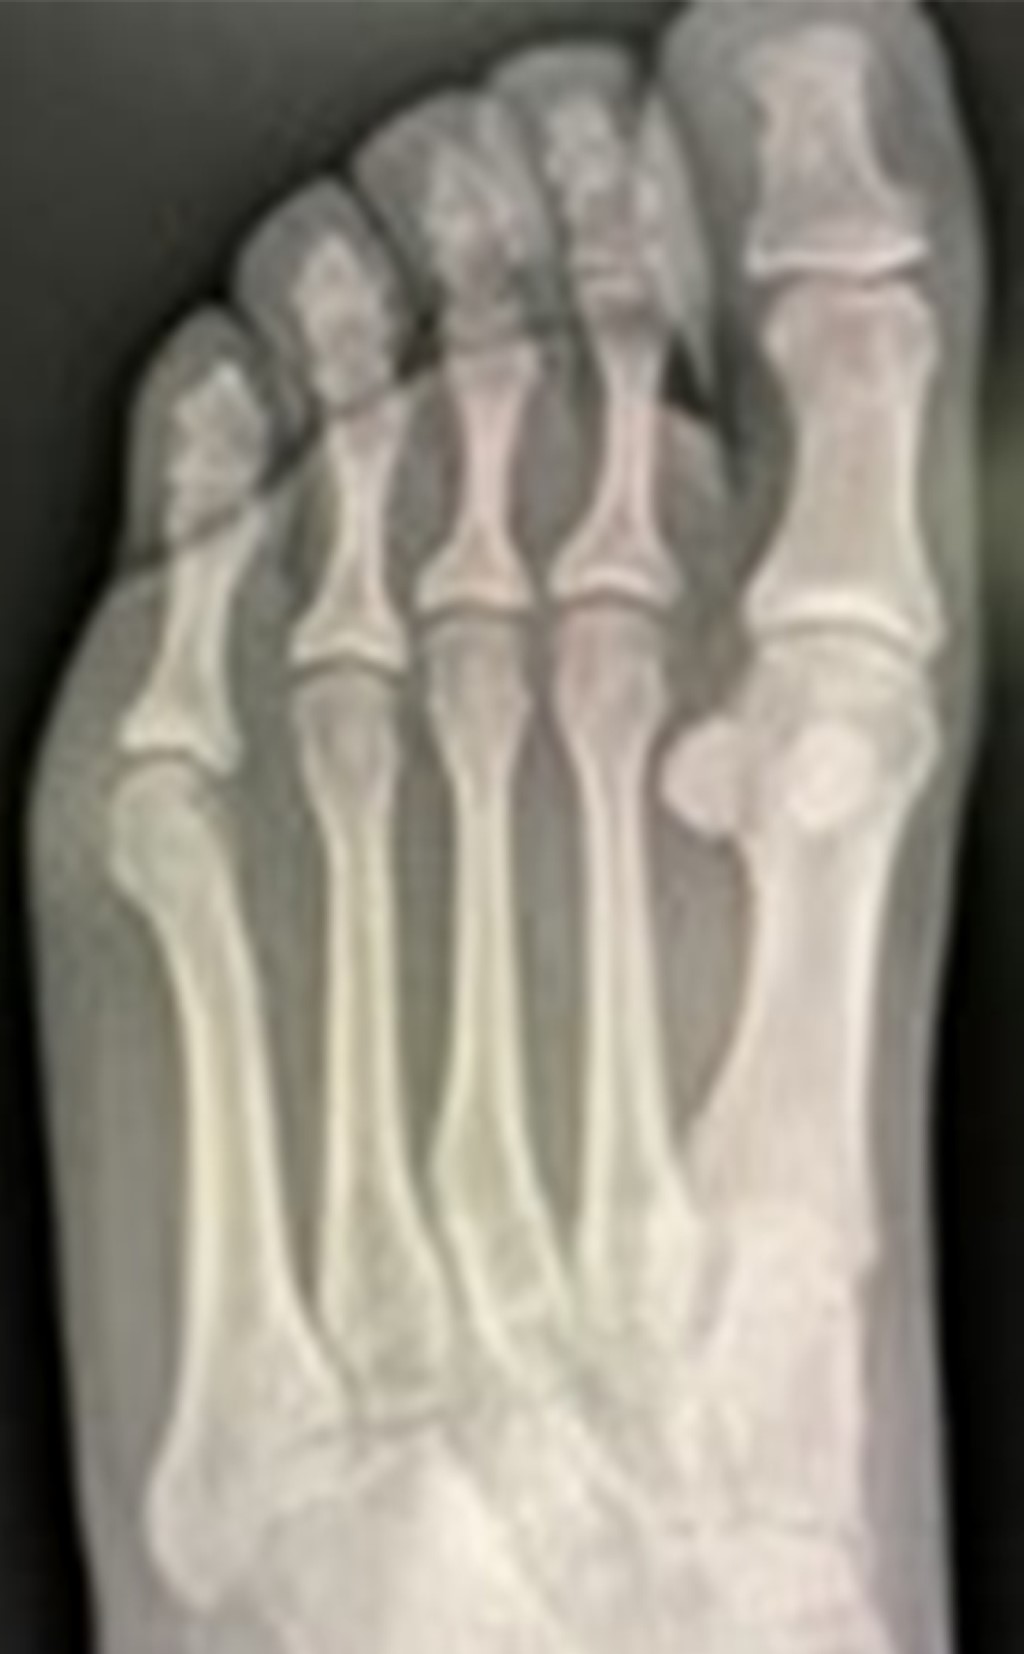

Caso clínico 2. Masculino de 15 años, sufre contusión directa en dorso del pie derecho al jugar fútbol, posteriormente inicia con dolor y marcha antiálgica, motivo por el cual acude a valoración. A la exploración física llama la atención el acortamiento del segundo dedo, con aumento de volumen y edema en dorso de articulación metatarsofalángica del segundo dedo. Se toman radiografías AP y oblicua de pie (Figura 4); evidencian fractura epifisiaria desplazada de la cabeza del segundo metatarsiano.

Con previo consentimiento de los padres y el paciente, se realiza reducción cerrada bajo anestesia local, se comprueba adecuada reducción con control radiológico (Figura 5). Se coloca zapato postquirúrgico y se inicia marcha a tolerancia. En seguimiento a corto, mediano y largo plazo sin evidencia de complicaciones; se anexan radiografías (Figura 6) a 30 meses de evolución.

Figura 4

Figura 5